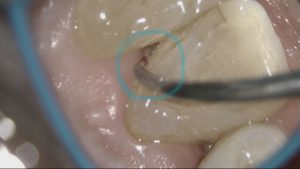

こちらの写真は、一番奥の歯と歯の間をマイクロスコープで撮影したものです。一番奥の歯の状態を患者さんへ伝えたくても鏡で見ていただくことはできません…。ですが、マイクロスコープを使えばこのようにお伝えすることができます。青マル部分が磨き残しになります。

歯と歯ぐきの溝からプラークがでてきます。

今のお口の状態をよくわかっていただけると思います。